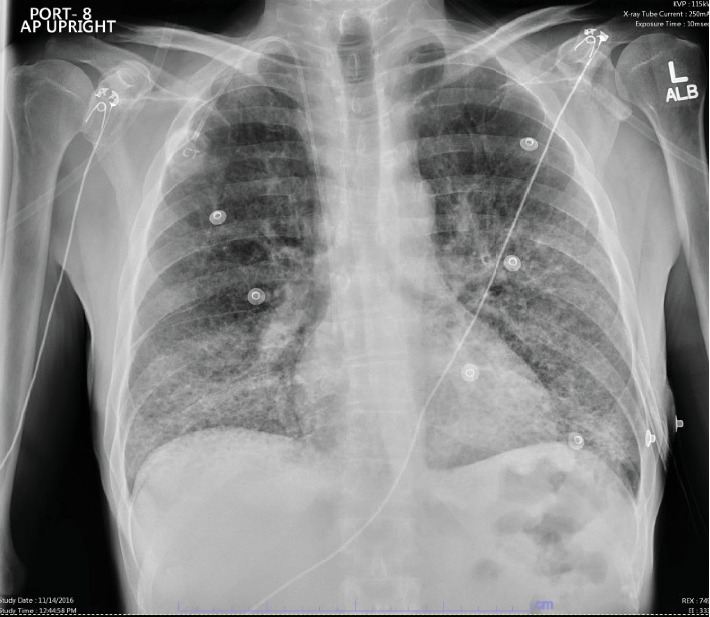

丝裂霉素C (MMC)肺炎导致急性呼吸窘迫综合征(ARDS)是一种罕见的危及生命的MMC不良反应。诊断MMC肺炎可能具有挑战性,因为更常见的病因(如细菌感染)往往是首先针对的目标,因为患者因化疗而免疫功能低下。我们报告了一例中年男性服用MMC而不同时服用长春花生物碱的病例,他发生了继发于MMC肺炎的ARDS,需要插管和重症监护。患者在服用抗生素多日后,经类固醇治疗恢复,未发现感染性病因。这个病例强调了认识到MMC是可能导致急性呼吸窘迫综合征和死亡的肺炎的潜在病因的重要性。

Mitomycin C (MMC) pneumonitis leading to acute respiratory distress syndrome (ARDS) is a rare and life-threatening adverse reaction to MMC. Diagnosing MMC pneumonitis can be challenging as more frequent etiologies such as bacterial infections are often targeted first due to patients being immunocompromised from chemotherapy. We report a case of a middle-aged male who was administered MMC without concomitant vinca alkaloid, who developed ARDS secondary to MMC pneumonitis requiring intubation and intensive care. The patient recovered with steroid treatment after being on antibiotics for many days, and no infectious etiology was ever identified. This case emphasizes the importance of recognizing MMC as a potential cause for pneumonitis which can lead to ARDS and death.